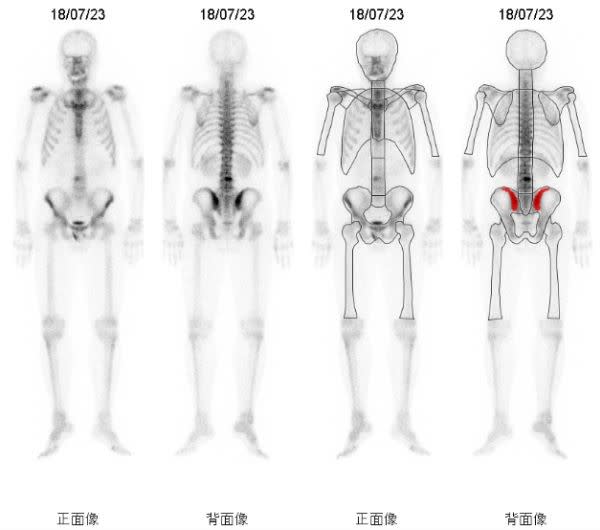

今年8月に前立腺癌の生検を受け10本中1本陽性でした グリソンスコア6psa155でした 9月骨シンチを受け1箇所集積があるとの事ただし1箇所である事と呼称は忘れましたがマーカーのような数字が0から1までの間で034と. 骨シンチ 40程に改善 足の痛み違和感ほぼ消える 身体に不都合何もなし 平成12年 4月 psa 05 骨シンチ 腰椎骨盤以外はほぼ消えた 左足は椅子に座っているとしびれの様なものを感じる程度 平成12年.

全身骨シンチグラフィ 乳癌 肺癌 前立腺癌等の骨転移病巣の検出

前立腺がんの検査 骨シンチグラフィー 前立腺がんの治療と名医

前立腺がんの検査 画像検査 Ct Mri 骨シンチグラフィ で何がわかる

全身骨シンチグラフィ 乳癌 肺癌 前立腺癌等の骨転移病巣の検出

骨シンチグラフィによる骨転移の診断 Bone Scan Ct Mri画像診断